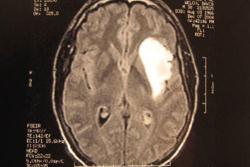

استفاده از روش ژنتیكی برای درمان سرطان مغز

محققان علوم پزشكی اعلام كردند با استفاده از كیسه های میكروسكوپی كه از سلول های مغز استخوان ساخته اند، موفق شدند سرطان را درمان كنند.

محققان در بیمارستان «هنری فورد» شهر دیترویت آمریكا اعلام كردند با استفاده از این روش ژنتیكی می توان به درمان مناسب برخی سرطان ها امیدوار شد.

دكتر «میشل چوپ» و همكارانش می گویند مرحله آزمایشی این روش را با موفقیت طی كرده اند.

دكتر چوپ اظهارداشت: تصور می كنم روش جدید ، روشی مناسب برای درمان سرطان باشد و مطالعه ما نشان می دهد با استفاده از این روش می توان به خصوص، سرطان مغز را به راحتی درمان كرد.

حققان توانستند با تزریق این كیسه های میكروسكوپی موسوم به اكزوزوم، تومورهای سرطان را ظرف مدت ده روز به طور بارزی كوچك كنند و از حجم این تومورها بكاهند.

دانشمندان می گویند با این روش می توان به درمان سرطان مغز امیدوارتر شد.(واحد مركزی خبر)